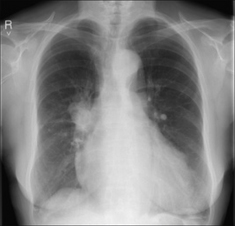

Figure 30.9 Haemoptysis secondary to elevated pulmonary venous pressure. In this case due to mitral valve disease. The sputum was pink and frothy rather than red.

CXR ABNORMAL (2) POSSIBLE CAUSE SUGGESTED